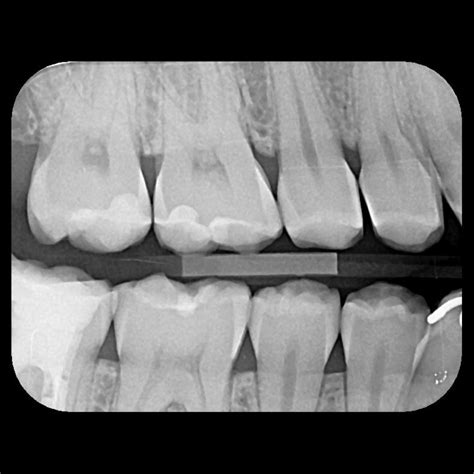

Caries interproximal en radiografías

- Detección de caries interdental: Las caries formadas entre los dientes suelen ser difíciles de detectar mediante una inspección visual, y con esta técnica se consiguen grandes resultados.

- Evaluación de restauraciones: Es útil para verificar el estado de los empastes, coronas y otros tipos de restauraciones dentales, asegurando siempre que estén bien ajustados y no haya filtraciones o desgaste.

Una de las principales utilidades de la radiografía de aleta de mordida es la detección de caries interproximales, es decir, aquellas que se desarrollan en el espacio entre los dientes. La radiografía de aleta de mordida también es clave en la evaluación del hueso alveolar, es decir, el tejido óseo que sostiene los dientes en su lugar. La pérdida de altura ósea puede ser un signo temprano de enfermedad periodontal.